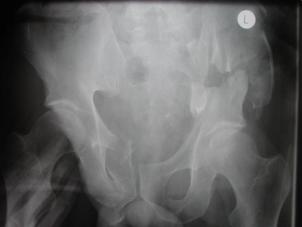

Fractura Malgaigne Fractura Malgaigne. Imagine CT

Fractura de

aripa iliaca stanga Fractura de aripa iliaca

stanga

Disjunctie sacro-iliaca stanga Disjunctie

sacro-iliaca stanga Aspect CT